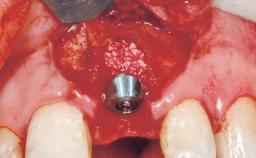

Immediate Flapless Placement of an Implant in a Maxillary Right Lateral Incisor Site

This 43-year-old male patient, a non-smoker, came to our practice because of a fracture of tooth 12 caused by a bicycle accident. Due to the combined para- and infrabony crown and root fracture, tooth extraction, and subsequent implant placement were suggested to the patient as the therapy of choice. The patient had high esthetic expectations with regard to the treatment outcome and asked for an immediate fixed provisional restoration. His individual esthetic risk profile summed up to a medium esthetic risk.

Placement Protocol Immediate implant placement

Loading Protocol Immediate

Retention Screw-retained Screw-retained